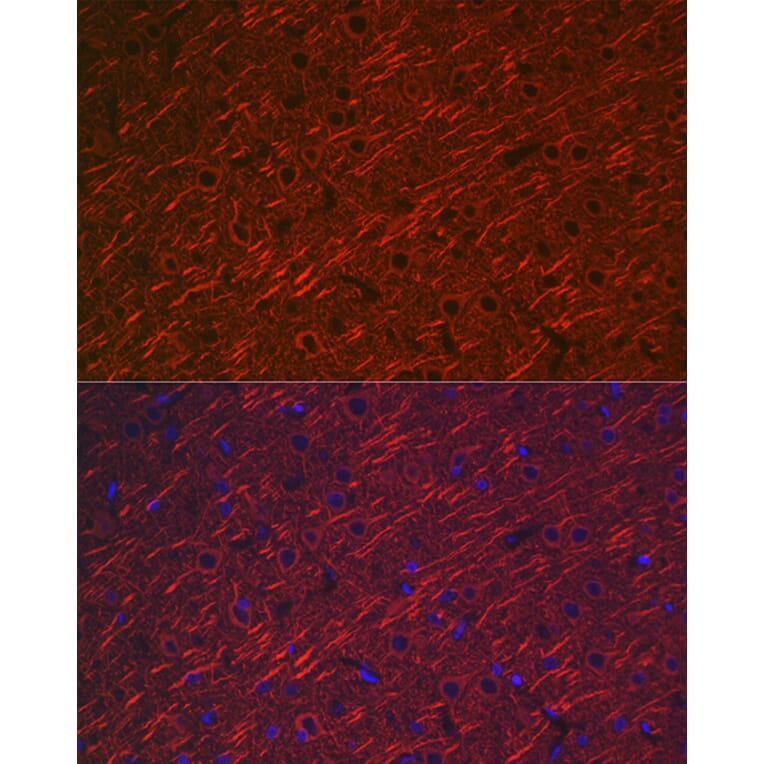

Parkinson's Disease (PD) is primarily characterized by a-synuclein pathology, which manifests as intraneuronal inclusions, neuroinflammation, and neurodegeneration. However, emerging evidence also points to significant vascular impairments as a critical aspect of PD pathology, which remains largely underexplored due to the inability of traditional in vitro models to recapitulate such vascular changes. To address this unmet need, here we combine the human organ-on-a-chip technology with the principle of vasculogenic self-assembly to engineer the capillary interface of dopaminergic neurons in the substantia nigra pars compacta of the midbrain. In our proof-of-concept demonstration, we successfully recreated critical neuronal pathology in PD, including a-synuclein aggregation, inflammatory responses, and progressive neuronal degeneration, by exposing our model to specially generated PD-associated a-synuclein preformed fibrils. Importantly, this engineering approach also enables the investigation of progressive vascular changes characteristic of PD, such as endothelial dysfunction, barrier disruption, and vascular regression. Our sophisticated PD model establishes a novel platform for exploring the multifaceted nature of the disease and understanding the complex interplay between neurodegeneration and vascular pathology, offering a unique tool for developing innovative therapeutic strategies that address both the neuronal and vascular components of PD pathology.